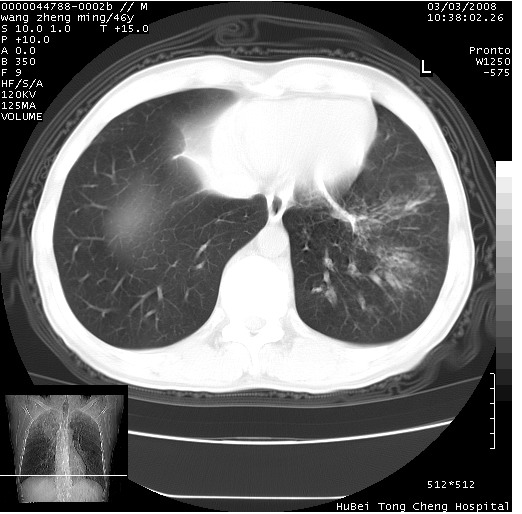

以下是引用卜一在2008-3-22 1:37:00的发言:[br]右肺实质性肿块,边缘不整,明显见毛刺征 分叶征及胸膜凹陷征,右上叶支气管明显变窄,远端散在的片状 斑片状实变影。另:左肺门较大肿块,支气管受累 变窄,远侧见阻塞性肺炎。纵隔内见肿大淋巴结。多考虑:右肺周围性肺癌伴左肺门 纵隔淋巴结转移!